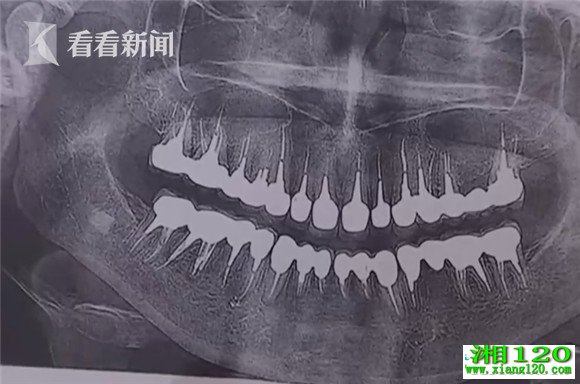

黑心牙医拔掉患者22颗健康牙齿 装质量不过关假牙

俗话说,牙疼不是病,疼起来要人命。俄罗斯一名患者在看牙医时不但要忍受病痛折磨,更是遇到了一件糟心事,她的牙医欺骗她需要安装假牙,居然拔掉了她的22颗健康牙齿。

据俄罗斯侦查委员会证实,圣彼得堡伏龙芝区一家私人诊所的医生兼创办人"在牙医服务问题上误导一名患者,拔掉了她的22颗健康牙齿,给她安了质量不过关的假牙"。这名女患者为此支付了84万多卢布,相当于1.5万多美元。